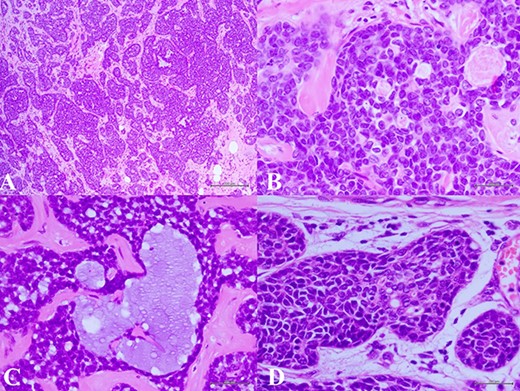

(A) Histologic examination showed the neoplastic cells predominantly arranged in a solid growth pattern (100×). (B) The true glandular spaces lined by luminal-type epithelial cells (600×). (C) The pseudolumens containing watery basophilic mucopolysaccharides basement membrane-like materials rimmed myoepithelial cells (400×). (D) Intraductal components composed of a dual population as the invasive areas (600×)

complex. The left axillary lymph node was found to measure 1 cm after palpation. A mammogram revealed an ill-defined mass at sub-areolar on left breast with angulation 2.3 × 1.9 cm, without suspicious microcalcification or architectural distortion (Fig. 1). Core needle biopsy revealed invasive ductal carcinoma (IDC). Immunohistochemical study (IHC) showed Estrogen receptor (ER), Progesterone receptor (PR), and Human epidermal growth factor receptor 2 (HER2) negative. Fine needle aspiration of left axillary lymph node revealed poorly differentiated metastatic lymph nodes. Metastatic workups were unremarkable. Left lumpectomy and axillary lymph nodes dissection were performed. The final pathology reported ACC measuring 3.5 cm in greatest dimension, lymphovascular invasion, presenting with DCIS, comedonecrosis type, high grade nuclei, microcalcification, all margins are negative for malignancy (Fig. 2). IHC showed CD117 and CK7 positive for malignant ductal cell of tumor, CK5/6 and p63 positive for myoepithelial cells within the tumor. ER, PR and HER-2 were negative. Ki-67 was strongly positive 3 + of nuclear staining, 30% of neoplastic cells (Fig. 3). One of 21 lymph nodes demonstrated metastatic ACC with extranodal extension (Fig. 4). Metastatic part is 0.9 cm in greatest dimension. Postoperative adjuvant chemoradiotherapy was given.